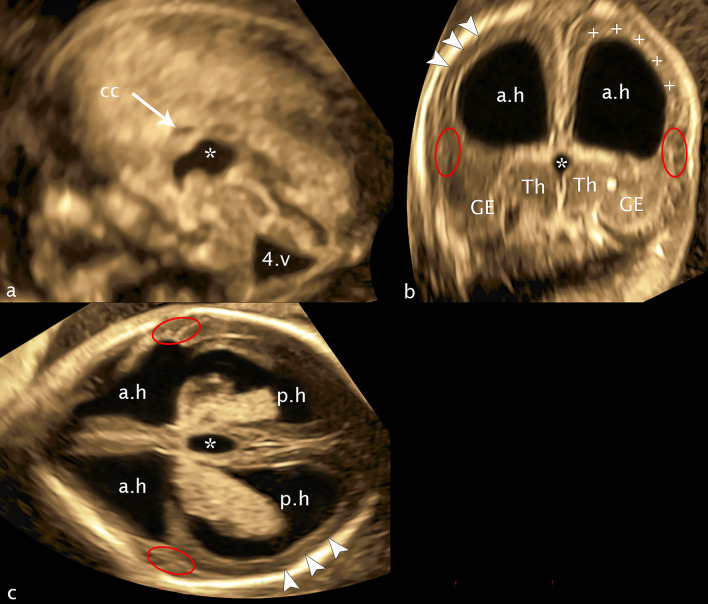

Fig. 13.

16 + 3 weeks of gestation. a sagittal plane b coronal plane c axial plane: cc—corpus callosum; a.h—anterior horn; p.h—posterior horn: Th—thalamus; asterisk—third ventricle; GE—ganglionic eminence; plus—band of echoghenicity; arrowheads—missed subarachnoid space; red ellipses—flat Sylvian fissure, one side bordered by a dysplastic cerebral mantle; 4.v—enlarged fourth ventricle

Fig 13: At week 16+3, the following diagnoses could be confirmed: severe dysplasia of the ganglionic eminences and the basal ganglia and a lack of the development of fissura Sylvii, both reflecting migrational disorder, ventriculomegaly on both sides, dilated 3rd ventricle, no adhesio interthalamica, hypoplasia of the corpus callosum and an outer band of echogenicity leading to the reduced subarachnoid space complete the supratenorial alterations. Infratentorially the hypoplasia of the vermis and transcerebellar diameter complete the total number of cerebral changes.